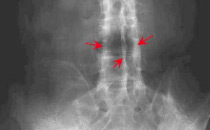

骶髂关节

例子

病症描述:AS较早的变化发生在骶髂关节。该处的X线片显示软骨下骨缘模糊,骨质糜烂,关节间隙模糊,骨密度增高及关节融合。